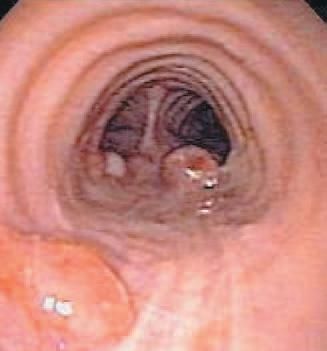

Diagnostic bronchoscopy revealed numerous polypoid lesions lining the trachea and bilateral main-stem bronchi. The lesions were of various sizes, from several millimeters to more than a centimeter in diameter, and were smooth without visible vessels or ulceration (Figure 6). The tracheal lesions were identical in appearance to the polypoid lesions in the main-stem bronchi.

Figure 6 – Bronchoscopy reveals multiple polypoid lesions lining the posterior wall of the trachea.